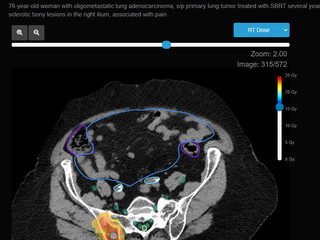

- Bone Metastasis 뼈전이의 방사선치료

- Bone Metastasis 뼈전이